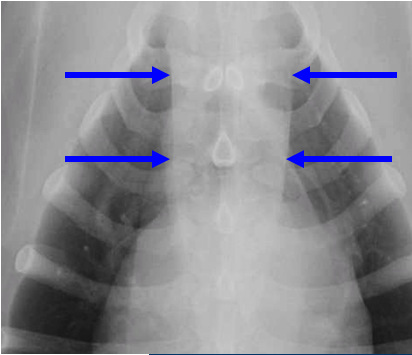

What can be seen here?

Cranial mediastinum

Midline, homogenous soft band

Shouldn’t be any wider than twice the width of thoracic vertebrae